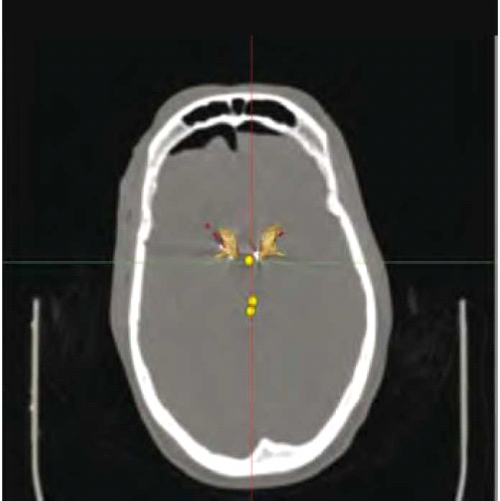

ההליך הניתוחי להשתלת קוצב לגירוי מוח עמוק בחולי אלצהיימר, דומה לזה המבוצע ביתר ההתוויות, כגון הפרעות תנועה, כאב כרוני והפרעות נפשיות, ומבוצע בשני שלבים: בשלב הראשון מושתלים הקוצבים המוחיים. ראשית, עוברים החולים הדמיה מוחית בתהודה מגנטית (Magnetic Resonance Imaging, MRI) (ראו איור 1) על מנת לשלול פתולוגיה העלולה לסכן את החולה במהלך הניתוח, כמו מפרצת (Aneurysm) מוחית, עיוות (Malformation) בכלי הדם או גידול. ביום הניתוח מונחת על ראש החולה מסגרת Stereotactic ובהמשך מבוצעת טומוגרפיה ממוחשבת (CT ,Computer Tomography) של המוח עם המסגרת (ראו איור 2). בגוף המסגרת ה-Stereotactic קיימים סמנים קבועים המהווים נקודות יחוס ומאפשרים למעשה להלביש את תמונת ה-MRI על גבי תמונת ה-CT. מהלך הניתוח מבוצע בערות מלאה של המטופל, ומתחיל בקידוח חור קטן בגולגולת דרכו תוחדרנה האלקטרודות למוח. השתל יוחדר תמיד קדמית לקליפת המוח האחראית על תנועה (Motor cortex). לאחר קדיחת החור, מוחדרות אלקטרודות למוח שתפקידן לבצע רישום מוחי אלקטרופיזיולוגי. רישום זה נותן לצוות המנתח התוויה בנוגע למיקום האלקטרודה, בעזרת זיהוי דפוסי הפעילות המאפיינים את אתרי המוח השונים ומהווים מעין חותמת שלהם. לאחר מיקום האלקטרודה בגרעין העמוק, מבוצע גירוי-מבחן במסגרתו מתבקש המטופל לבצע מטלות התנהגותיות המאתגרות את התפקוד הפגוע, כמו זיכרון בחולי אלצהיימר או רעד בלוקים בהפרעות תנועה. מטרת הבדיקה ההתנהגותית היא לוודא את מיקומה של האלקטרודה ולשלול תופעות לוואי מהגירוי, שיחייבו מיקום מחדש של האלקטרודה. הליך זה מבוצע בשני צדי המוח.